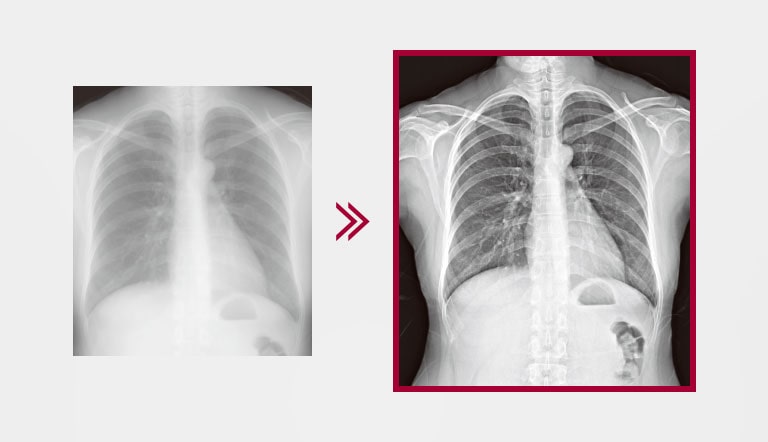

Disponibilidad Rápida de Imagen

Disponibilidad de la imagen en 2 segundos con una conexión por cable o 2.5 segundos con una conexión inalámbrica para obtener una imagen en bruto